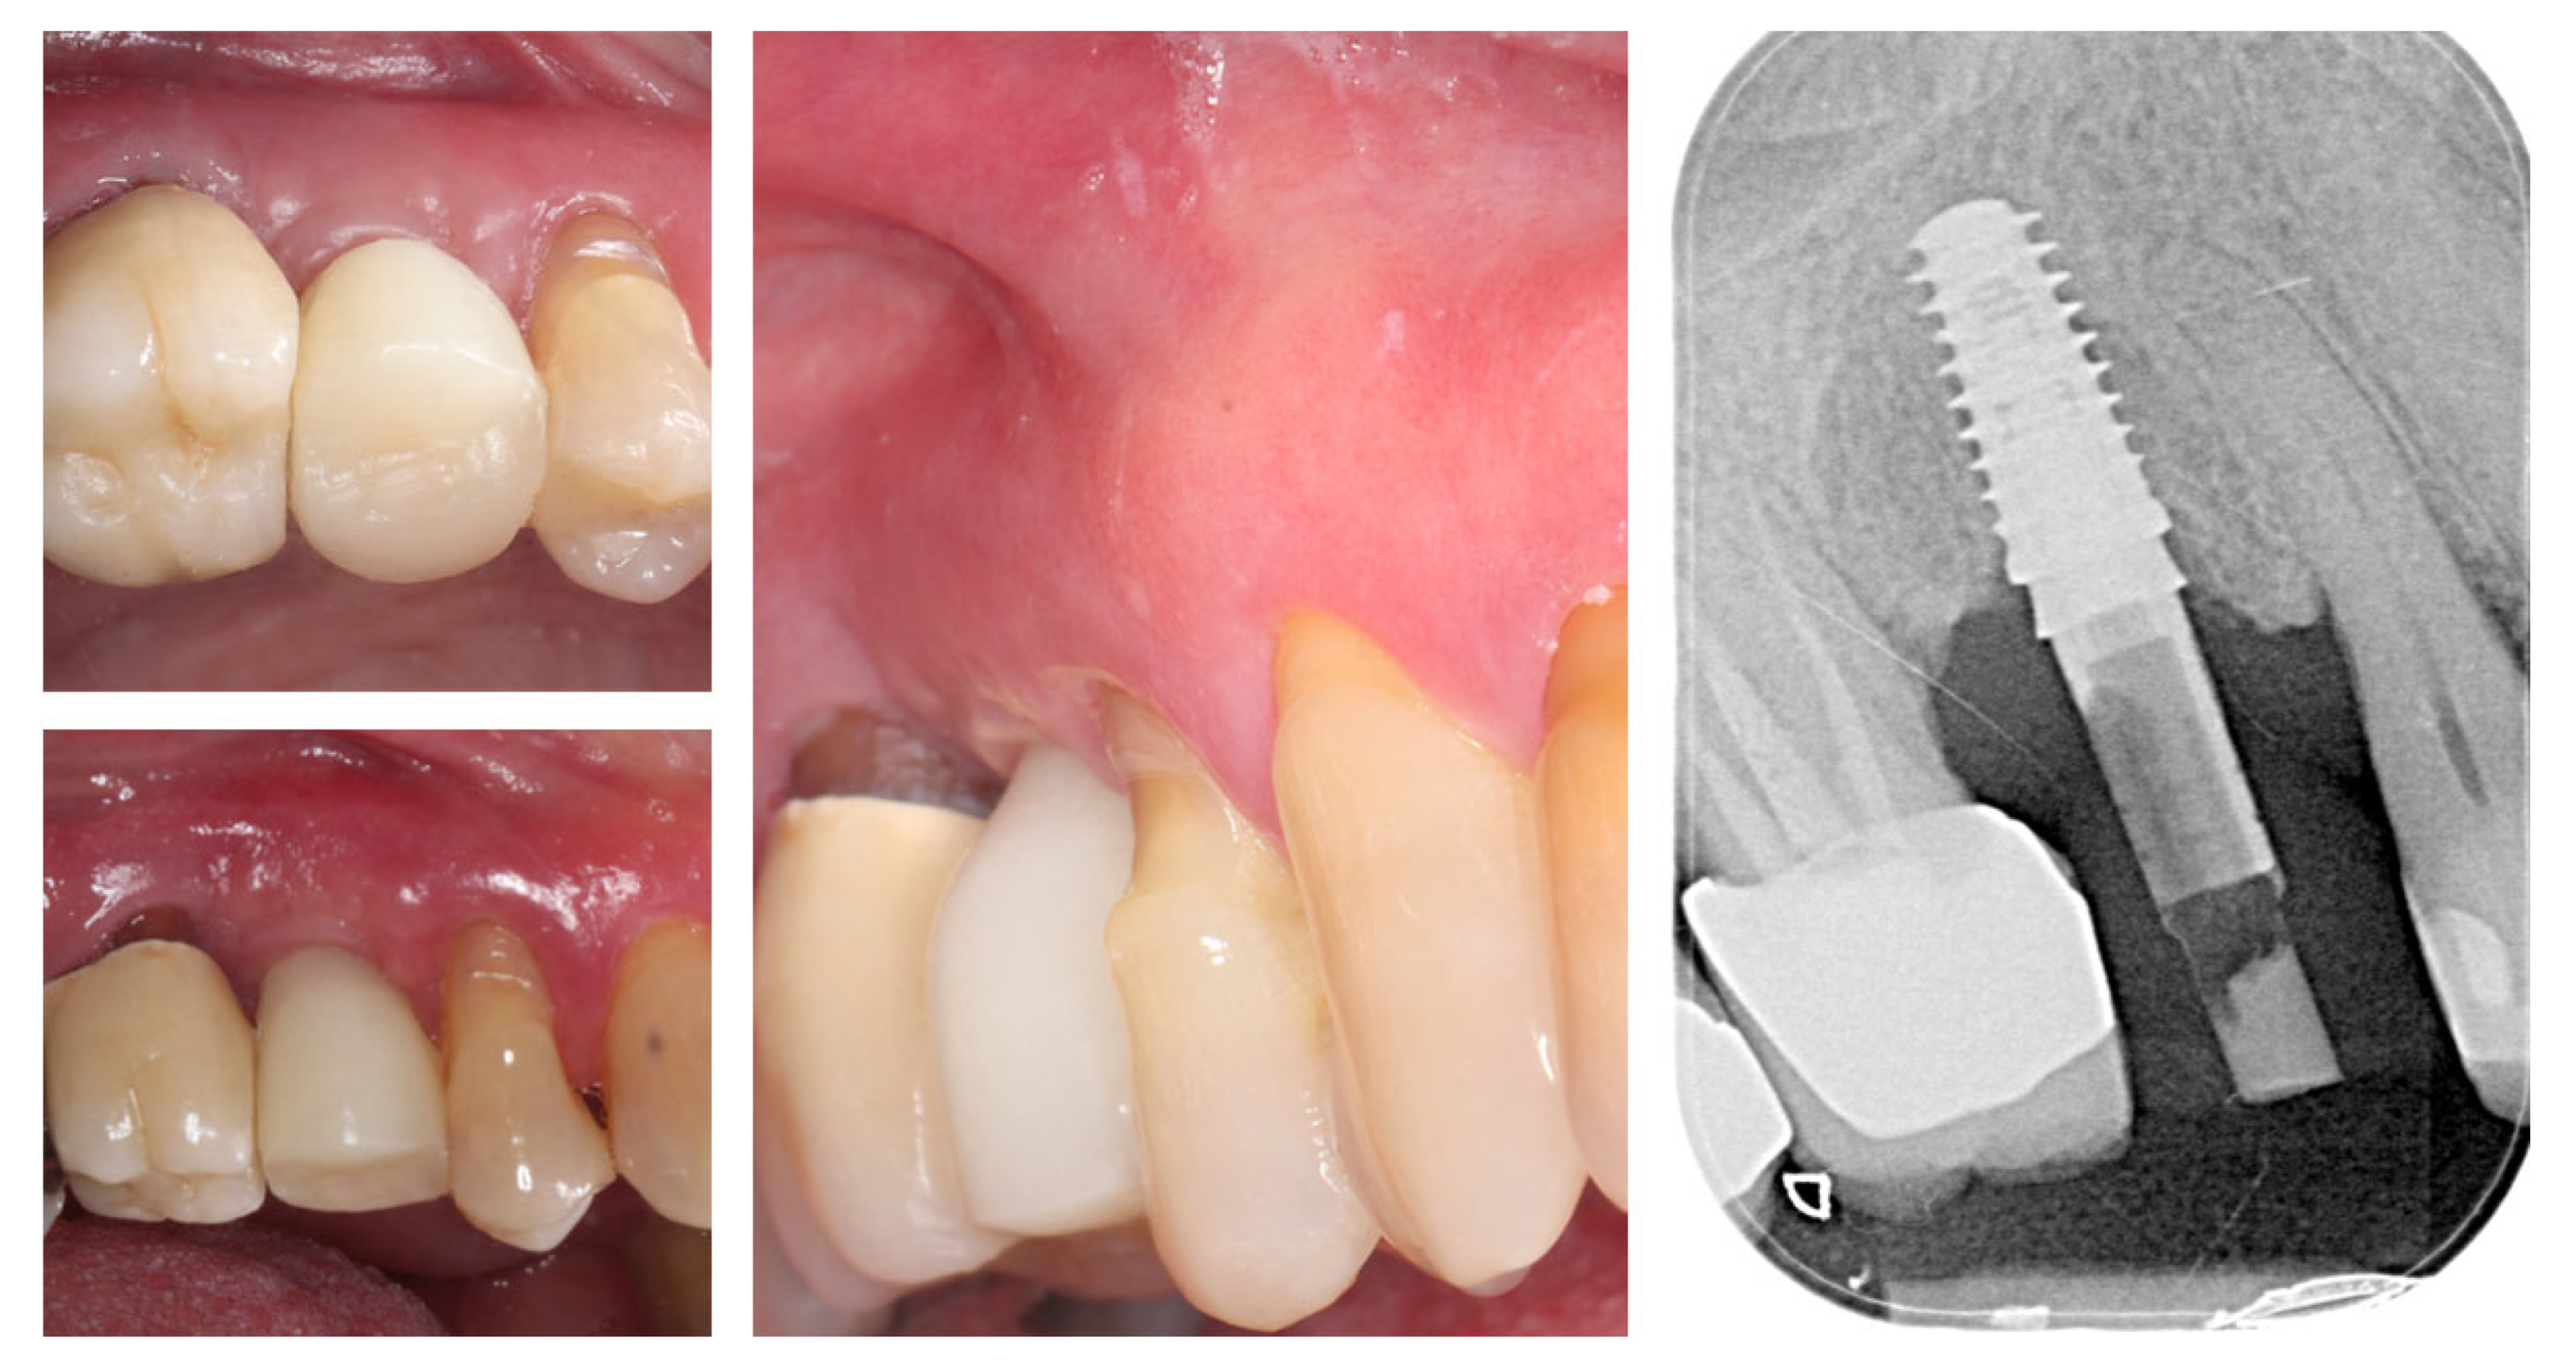

| Timepoint | Horizontal Thickness (mm) | Vertical Thickness (mm) | Clinical/Radiographic Findings | |

|---|---|---|---|---|

| 1 | Baseline (Day 0) | 2.3 | 2.4 | Initial thin buccal tissue |

| 2 | 2 weeks post-op | Uneventful healing, stable mucosal margin | ||

| 3 | 3 months post-op (with provisional) | 3.4 | 3.4 | Increased thickness, stable bone and mucosa |

| 4 | 4 months post-provisional | 3.5 | 3.6 | Stable peri-implant mucosa around provisional crown |

| 5 | 8 months post-op (final crown) | 3.5 | 4.1 | Final crown placed, harmonious soft tissue contours, and stable crestal bone |

| 6 | 14 months post-definitive | Long-term stability of soft tissue and crestal bone confirmed |